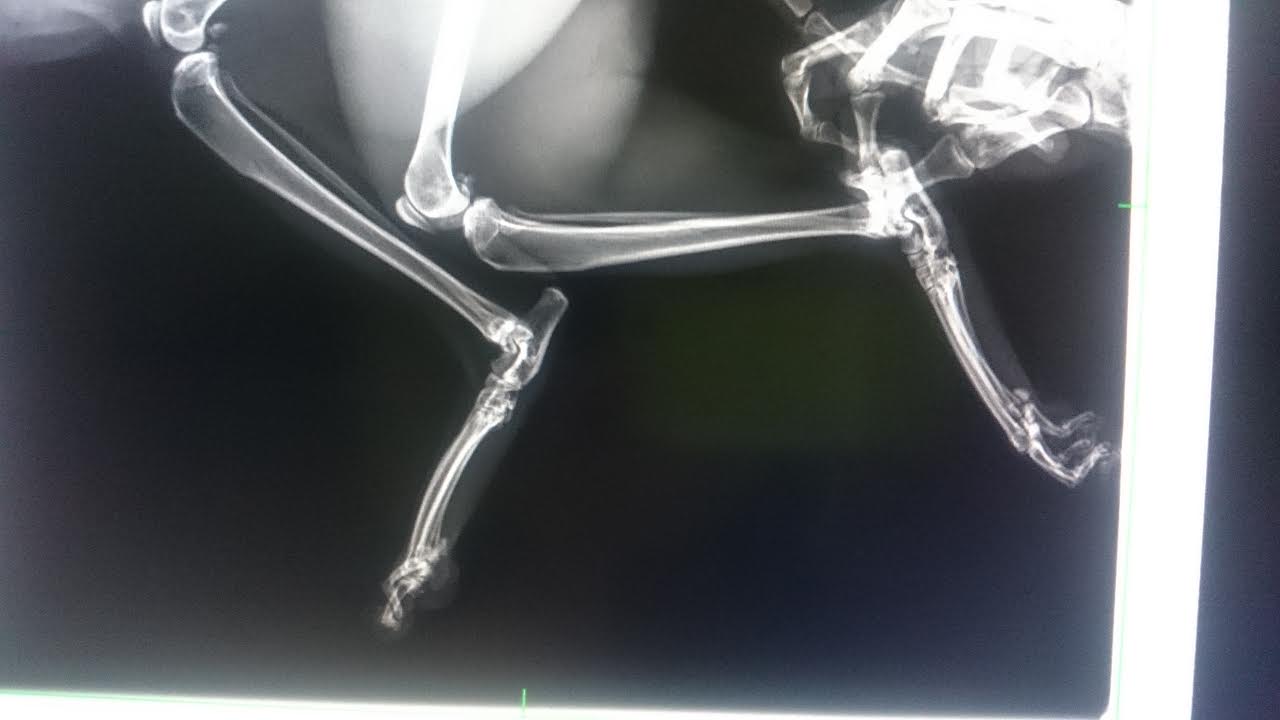

2. 左前指外傷,右後掌缺損(舊傷)